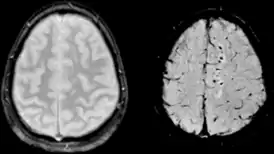

![]() Диффузное аксональное повреждение на МРТ в режиме GRE (слева) и SWI (справа) | |

При диффузном аксональном повреждении головного мозга микроскопические мелкоочаговые кровоизлияния выявляются в мозолистом теле, полуовальном центре, верхних отделах ствола мозга. Клинически оно проявляется длительной комой, которая в большинстве случаев переходит в вегетативное состояние. Последнее характеризуется отсутствием корковой деятельности и длится месяцы и годы.